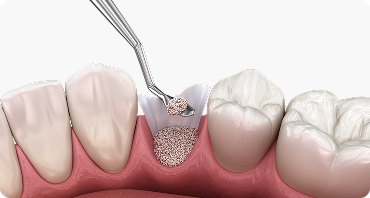

뼈이식 임플란트

임플란트에서 중요한 부분은 두꺼운 뼈와 건강한 잇몸에 있습니다.

뼈가 안 좋아 임플란트가 어려울 경우, 임플란트 식립을 위해

약해진 잇몸뼈를 이식하여 임플란트의 장기적인 수명을 향상시킵니다.